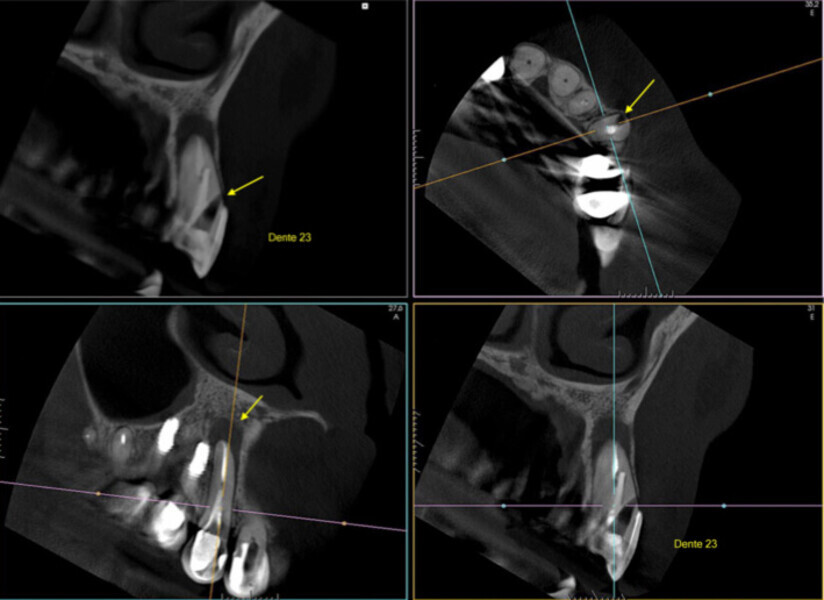

Fig. 1: A cone beam computed tomography was performed for diagnosis and to establish a treatment plan. (Photos/Provided by Renato Interliche, Douglas Giordani Negreiros Cortez and Clauber Romagnoli)